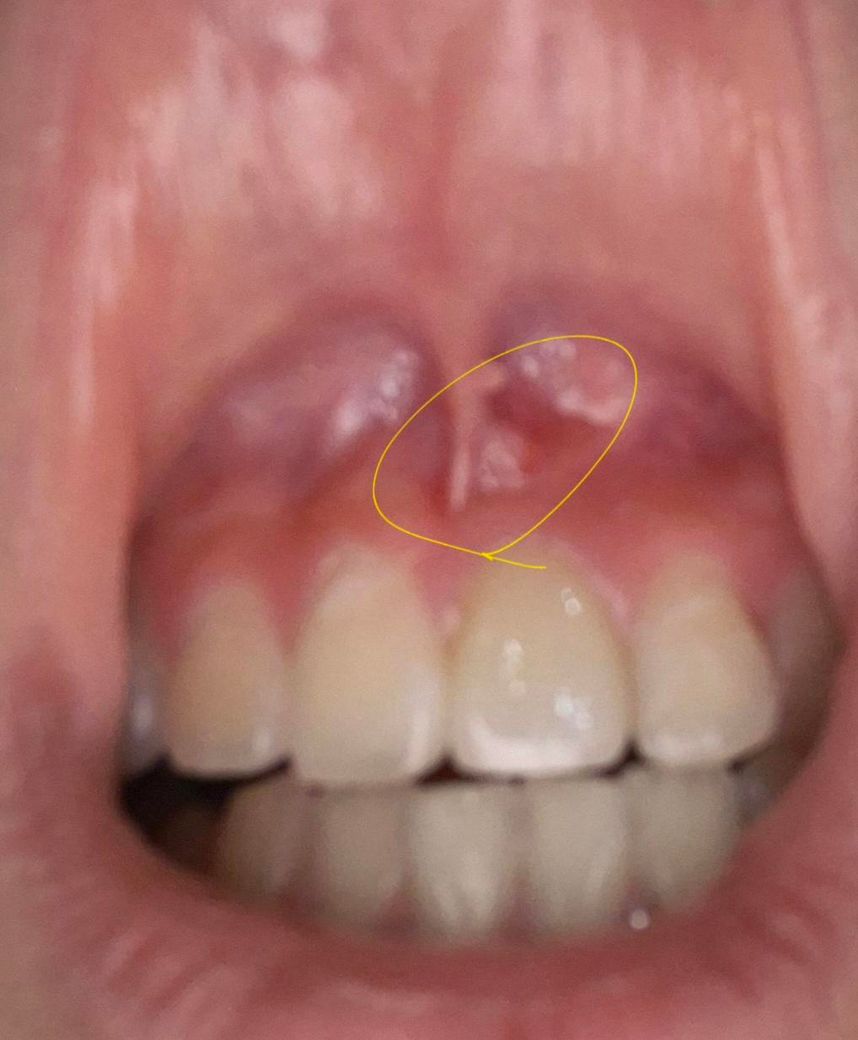

잇몸에 작은 이물감이 있어요 어떻게 해야 하나요?

일어나서 잇몸에 이물감이 들어서 봤더니 이래서요

뭔지 궁금합니다 큰일인가요? 피가 가거나 하진 않아요

어떻게 해야 할지 모르겠습니다 치료한지 얼마

안 됐는데..

사진으로 봤을 때는 근단치주염일 가능성이 높습니다. 치아 내부에 신경이 감염이 되면 뿌리 쪽의 염증을 형성하게 되는데 이런 염증이 외부로 드러나게 되면서 사진과 같이 고름이 찰 수 있습니다. 이런 경우 재신경치료나 치근단 말이 절제 설정이 필요할 수 있습니다.

잇몸이나 치아 속 신경의 염증 때문에 농양이 잡혔습니다 배농을 해주고 잇몸치료 내지는 신경치료를 해야 합니다